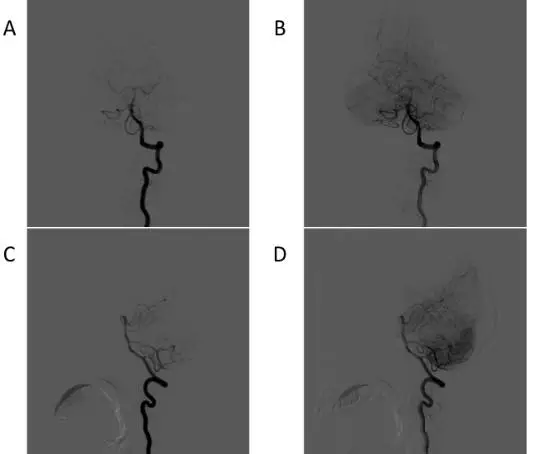

图4. 术前左侧椎动脉造影提示:椎动脉系统不参与供血。

手术经过:在复合手术室(Hybrid operation room),患者经气管插管全身麻醉后。首先经右侧股动脉穿刺置鞘,选用造影导管超选至左侧颈外动脉进行造影,并利用不透射线的刻度尺进行定位(图5A)。在正侧位造影后,利用刻度尺的定位左侧脑膜中动脉靠近瘘口且较为平直的一段,画出该段血管的体表定位(图5B、5C)。根据该段血管的体表投影线做一直切口(图5D),暴露该段脑膜中动脉,结扎近心端后,剪开硬脑膜,离断该段脑膜中动脉,在不塑形的0.014in的Synchro微导丝带领下,直接通过血管断端远端插入Echelon-10微导管(图6A)。通过手推造影确认微导管插入血管为靶血管后(图6B),在路图条件下(图6C),在Synchro微导丝带领下将Echelon-10微导管超选至瘘口,并通过手推造影确认微导管位置(图6D)。随后,缝扎血管断端远端,利用缝线扎紧微导管,阻断注胶时的反流,即“高压锅技术”。造影导管依次超选至双侧颈外动脉,在造影的监测下,阴性路图下通过Echelon-10微导管注入Onyx-18胶1.5ml。复查造影,见瘘口完全被栓塞,引流静脉消失。遂撤除微导管,结束手术(图7)。

图5. A 术中定位用不透射线的刻度尺。B/C 利用刻度尺进行标记,术中正侧位造影,定位左侧供血的脑膜中动脉分支靠近瘘口较为平直的一段。D 平行横窦的黑线即脑膜中动脉的体表投影线。近心端和远心端两条垂直于横窦的标记线标记处为该脑膜中动脉较为平直的一段,长度约5cm。中间黑框所示范围内即直切口区域。

图6. A 直切口切开皮肤,骨瓣约直径2cm大小,暴露靶血管。离断近端血管后,通过血管断端远端插入Echelon-10微导管。B 术中手推造影确认微导管插入血管即靶血管。 C 微导管内路图显示瘘口。D 手推造影确认微导管超选到位。